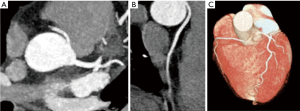

As usual management within the precordial pain protocol in the emergency room, Coronary Artery Angiography is performed. This shows an RCA with anomalous origin in the left Valsalva sinus, interarterial pathway and luminal loss at this level.

The case of patient number 2 is completely different. In this case, despite the history of negative ischemia induction tests, it presents an evident compression in the interarterial pathway (Figure 3). This is evidenced by both the Coronary Angio CT and the Coronary Artery Angiography. This is important because despite initially negative ischemia tests, any kind of compression or obstruction that compromises the vascular caliber should always be carefully discarded. Accordingly to clinical practice guidelines, these patients are also candidates for revascularization for symptomatic improvement and risk of SD reduction, despite the presence of negative ischemia detection tests.